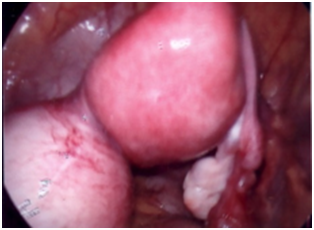

27 years old lady, para 2 reported with pain abdomen of many months duration. Pain was intermittent initially but had become almost continuous and was dull aching in character. She had two normal vaginal deliveries. Her general and systemic examination was normal. Gynecological examination revealed a normal size uterus with adnexal mass of 10 to 12 cm, globular mass which had restricted mobility. Ultrasound suggested large endometriotic cyst. She was posted for diagnostic laparoscopy which showed an enlarged and distended rudimentary horn on right side (Figure 3) (Figure 4). Since the mass was big size and endoscopic surgical expertise was not available, hence laparotomy was done and rudimentary horn along with ipsilateral fallopian tube was excised. The cavity contained a large quantity of chocolate material. She made an uneventful postoperative recovery.

Figure 3 Hematometra along with non distended uterine body on laparoscopy.

Figure 4 Hematometra on right side on laparoscopy.